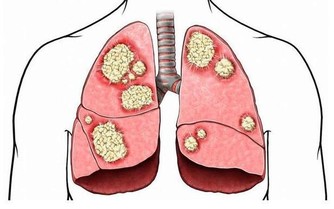

雖說懶不是病,但有時候,懶起來也要人命!這不是危言聳聽,一旦被“懶”附身,許多疾病,包括癌症都將接踵而至。

此外,人若缺乏光照,維生素D便合成不了,而維生素D缺乏,又與癌症、糖尿病、中風、心髒病、硬化症、結核病、骨質疏鬆以及呼吸道感染等有關。所以,想要防寒保暖,遠離疾病,這個冬日不妨多曬太陽。

★建議:每年至少體檢一次,檢查的重點項目是心、肺、肝、膽、胃等重要器官,以及血壓、血糖等重要指標。